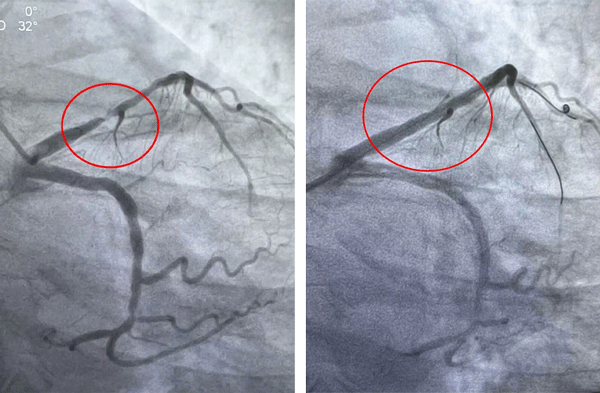

▲术前 ▲术后

另一例患者郝先生发病超24小时就诊,冠脉造影显示冠脉多发重度狭窄,右冠脉远段狭窄达95%,且血管走形迂曲、合并严重钙化,介入治疗难度极高。面对挑战,介入团队凭借熟练的技术与密切配合,历经两小时精准操作,成功完成右冠脉血运重建。